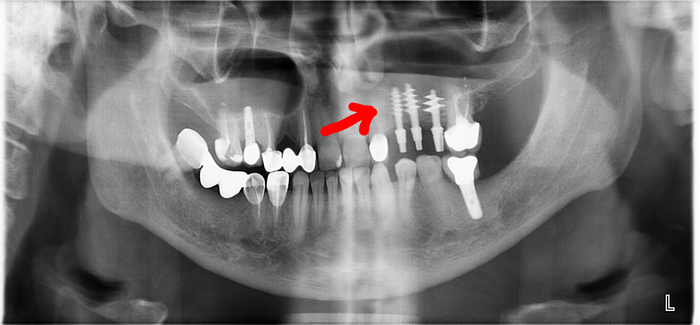

Еще одна:

Стрелками отмечены самые явные участки деструкции кости.

Такая вот простая и хорошая имплантация.